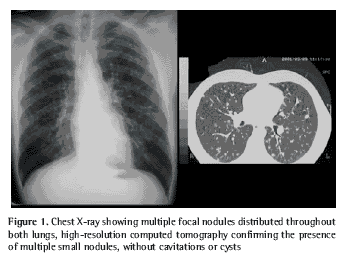

The chest X-ray showed multiple focal nodules in both lungs. High-resolution computed tomography confirmed the presence of these small nodules, the largest of which measured 10 mm in diameter. The lesions were located predominantly in the upper lobes and, to a lesser extent, throughout the medial pulmonary fields, sparing the bases and the costophrenic angles. There were no cysts or cavitations within these small nodules. No enlarged lymph nodes were detected (Figure 1).